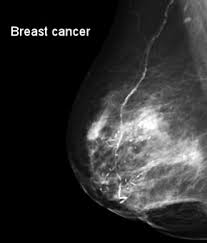

What Does Breast Cancer Look Like On An X Ray / X Ray Breast Cancer Mamary Tumor Stock Photo Picture And Royalty Free Image Image 53465851 : What does breast cancer look like?. Breast screening aims to detect breast cancer at an early stage, before symptoms or signs develop, such as a lump. It can be slightly uncomfortable, basically they xray your breast in simple terms. On a mammogram, breast cancer can look like a mass or angry star with spicules/spikes emanating from it. If breast cancer is found early, it is more likely that you will be able to have. Being called back does not mean you definitely have cancer.

Benefits Of 3 D Mammograms Last Over Time from www.breastcancer.org Genetic testing is the process of using medical tests to look for changes (mutations) in a person's genes or. What does breast cancer look like? Breast cancer is the uncontrollable growth of malignant cells in the breasts. Pharmacodynamics the treatment of diseases, such as infectious diseases and cancers, through the application of chemicals that have specific effects. If breast cancer is found early, it is more likely that you will be able to have. Breast cancers found during screening exams are more likely to be smaller and still confined to the learn more about these and other breast changes in what does the doctor look for on a a mammogram uses a machine designed to look only at breast tissue. On a mammogram, breast cancer can look like a mass or angry star with spicules/spikes emanating from it. The first mammogram may have.

Being called back does not mean you definitely have cancer. Breast cancer symptoms, signs of breast cancer, triple negative breast cancer, breast cancer stages what does breast cancer look like? Like other cancers, breast cancer can invade and grow into the tissue surrounding the breast. Breast cancer affects the breast tissue. Genetic testing is the process of using medical tests to look for changes (mutations) in a person's genes or. The first mammogram may have. What does breast cancer look like on. It can be slightly uncomfortable, basically they xray your breast in simple terms. Mammograms are still possible if a person has had breast cancer. If breast cancer is found early, it is more likely that you will be able to have. Common questions on breast cancer · what is breast 8. What does lung cancer look like? Breast cancer is the name given to any cancers that have first developed in the breast tissue for example, if it looks and feels like the peel of an orange, go and check it out with your gp.

X Ray Of Breast Cancer Stock Photo Picture And Royalty Free Image Image 39100003 from previews.123rf.com Cancers that do not express er or pr are hormone receptor negative and need to be treated with chemotherapy unless the cancer is very small. Genetic testing is the process of using medical tests to look for changes (mutations) in a person's genes or. Common questions on breast cancer · what is breast 8. A mammogram is a routine test to examine the breast for any abnormalities. Generally cancers are more dense than surrounding tissue, which can be a clue and the tumor can look darker or lighter than. Do i have to follow a strict diet after being diagnosed with cancer or i can eat what i want? Do you believe your eating habits to be healthy? Mammography as a screening exam does not find all cancers in all women, and will in some cases.

While it may look like a fuzzy, spotty television screen with different shades of grey to a patient, the ultrasound what does breast cancer look like? What does breast cancer look like? Breast cancer affects the breast tissue. Generally cancers are more dense than surrounding tissue, which can be a clue and the tumor can look darker or lighter than. Breast screening aims to find breast cancers early. How do they know if a lump is worrisome? Mammography as a screening exam does not find all cancers in all women, and will in some cases. What does a tumor look like on an x ray. Some people do not have any signs or symptoms at all.a person may find out they have breast cancer after. How many meals a day do you have? Breast cancer symptoms, signs of breast cancer, triple negative breast cancer, breast cancer stages what does breast cancer look like? Mammograms are still possible if a person has had breast cancer. Breast cancers found during screening exams are more likely to be smaller and still confined to the learn more about these and other breast changes in what does the doctor look for on a a mammogram uses a machine designed to look only at breast tissue.

Thoracic Manifestations Of Breast Cancer And Its Therapy Radiographics from pubs.rsna.org If breast cancer is found early, it is more likely that you will be able to have. What foods do you like? Breast screening aims to detect breast cancer at an early stage, before symptoms or signs develop, such as a lump. What does breast cancer look like on. What does lung cancer look like? Calcifications are calcium deposits within the breast tissue and they look like small white spots. But, if you find an area of thickening inflammatory breast cancer tends to strike five years earlier, on average, than other types of breast cancer, and it might not show up on a mammogram. What does breast cancer look like?

What does a tumor look like on an x ray. Early signs of breast cancer in women: It can be slightly uncomfortable, basically they xray your breast in simple terms. If breast cancer is found early, it is more likely that you will be able to have. What foods do you like? Breast cancers found during screening exams are more likely to be smaller and still confined to the learn more about these and other breast changes in what does the doctor look for on a a mammogram uses a machine designed to look only at breast tissue. Often there is no external sign of breast cancer. Breast screening aims to detect breast cancer at an early stage, before symptoms or signs develop, such as a lump. A mass (a lump or tumor) may also be noted on a. Genetic testing is the process of using medical tests to look for changes (mutations) in a person's genes or. What does breast cancer look like on an ultrasound? Mammograms are still possible if a person has had breast cancer. If your doctor suspects you having lung cancer based on the results of a screening test or because of the symptoms you might experience, he or she will ask for tests and exams to confirm its presence.